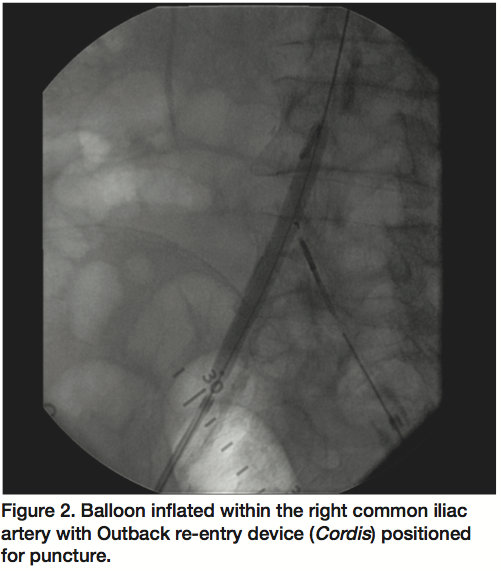

A 72-year-old male with a 5-year history of lifestyle limiting bilateral lower extremity claudication was evaluated by peripheral angiogram. Right femoral angiogram revealed total occlusion of the right common iliac artery (CIA). Left femoral angiogram revealed total occlusion of the left CIA. The length of occlusion was noted to be 5 cm on the right and 10 cm on the left. Subsequent aortogram from left brachial artery access confirmed complete occlusion of the distal abdominal aorta with collaterals filling both iliac arteries (Figure 1). A Wildcat CTO device (Avinger, Redwood City, California) was advanced retrograde through the right CIA occlusion to successfully cross into the distal abdominal aorta with intraluminal position confirmed by contrast injection. Balloon angioplasty was performed within the right CIA with an Evercross 8 x 80 mm balloon (ev3 Inc., Plymouth, Minnesota) with modest improvement of stenosis and significant vessel recoil. The Wildcat device (Avinger) was then advanced retrograde through the left CIA occlusion but entered a subintimal dissection plane. After multiple unsuccessful attempts with wires and support catheters to cross into the true lumen, an Outback Re-entry device (Cordis Endovascular, Warren, New Jersey) was used to attempt re-entry. Due to significant distal aortic disease and vessel recoil, the puncture needle and wire were unable to re-enter the true lumen. The Evercross 8 x 80 mm inflated balloon (ev3 Inc.) was then positioned in the distal aorta as a target for the Outback catheter (Cordis) (Figure 2) while the needle was advanced to puncture the balloon. The wire was then advanced into the abdominal aorta with intraluminal position confirmation with contrast injection. Bilateral CIA simultaneous kissing balloon angioplasty was then performed without complication, with reconstruction of the aortoiliac bifurcation using a total of 4 balloon expandable covered stents. Final angiogram showed a patent abdominal aorta and bilateral CIA with brisk flow down both lower extremities (Figure 3).